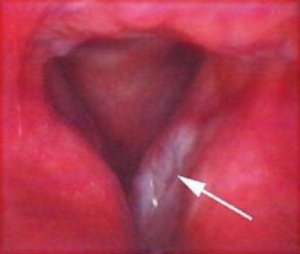

На первичном этапе применяется ларингоскопия. Рак гортани фото имеет разную локализацию. Ларингоскопия определит эндоскопические смены в горле. Типология образования определяется по биопсии. Дополнительно при подтверждении диагноза применяется интраоперационная диагностика, диагностика голосовой функции, МСКТ, рентгена.

Рак гортани фото